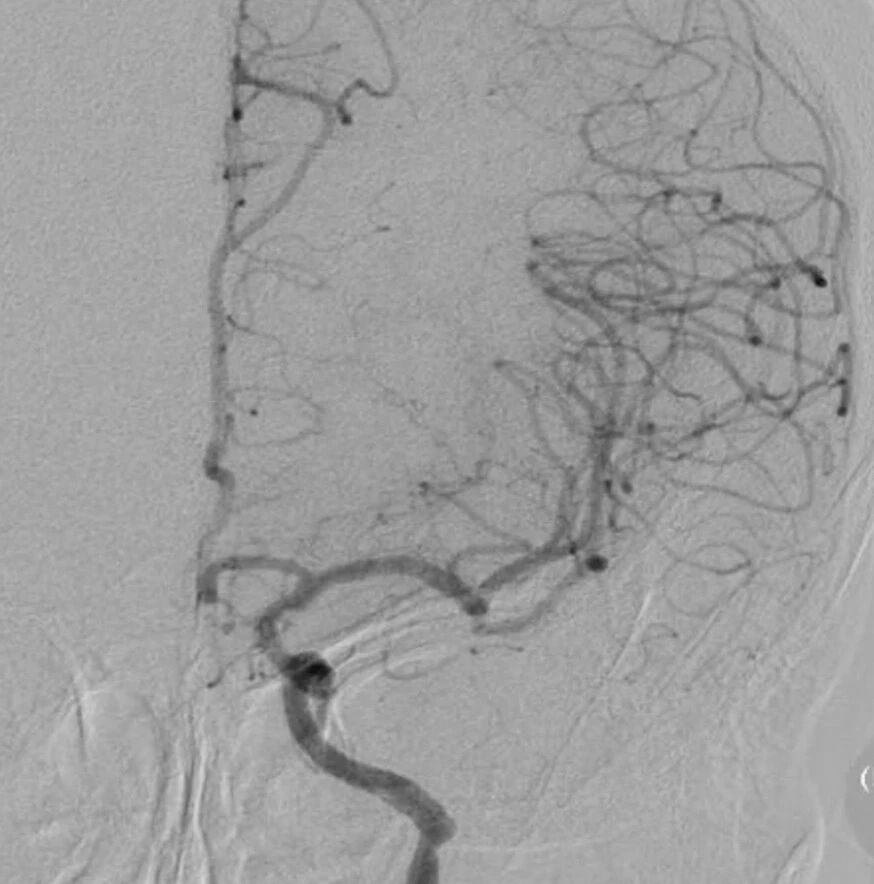

脑血管造影提示右侧颈内动脉颅内段多发动脉瘤(反主动脉弓)

脑血管造影提示右侧颈内动脉颅内段多发动脉瘤